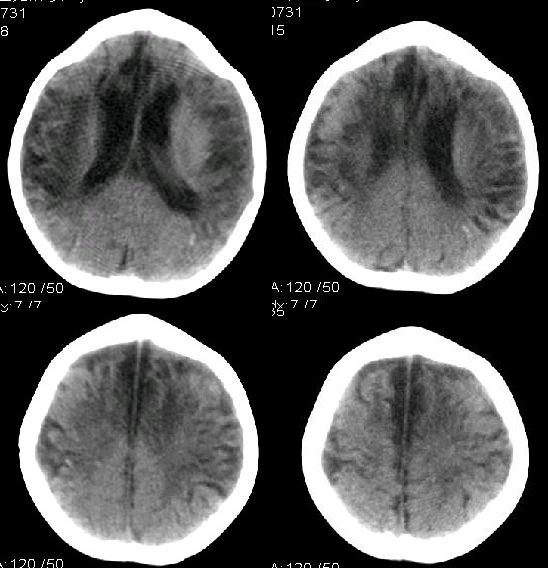

2岁智低体弱女婴脑部ct平扫示

皮质变薄(脑沟裂增宽)伴灶性梗死(小灶脑脊液样低密度影)、

白质减少(脑室增大)并变性(脱髓鞘所致的较对称分布的灶性近似脑脊液密度的低密度灶,个别与脑室穿通)、

颞枕叶交界脑质近凸面点索样钙化灶

鉴别:1、重度hie后遗改变 hie一般不会出现点索样钙化灶;

2、结脑后遗改变 结脑出现钙化的机会更多,呈斑片状,且往往在脑底部,脑质改变往往不如脑室改变(交通性脑积水)更显著